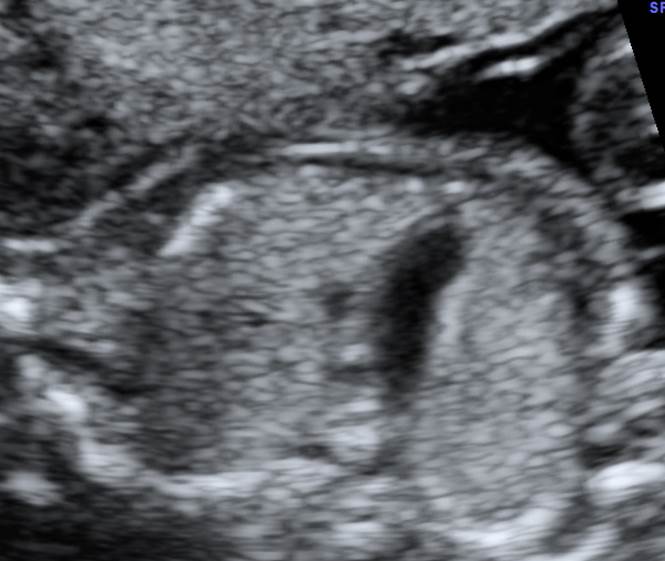

Вопрос 11

Поставьте диагноз

• А — норма;​

• Б — АВ-канал ;​

• В — транспозиция магистральных сосудов;

• Г — гипоплазия левого желудочка

Ответ на вопрос 11